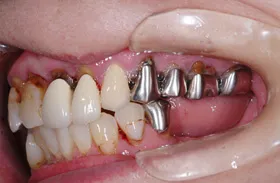

他院で「歯槽膿漏は治らない」と言われ、当院にご来院されました。歯が乱ぐいのため、歯並びもよくしたい、下は歯を既に失っているので噛めるようにもなりたい、またコーラスをされていて人前で口をあけることが多いので、できるだけ見た目を意識した治療をしてほしいとのご要望でした。

■治療前

■治療(仮歯装着)後